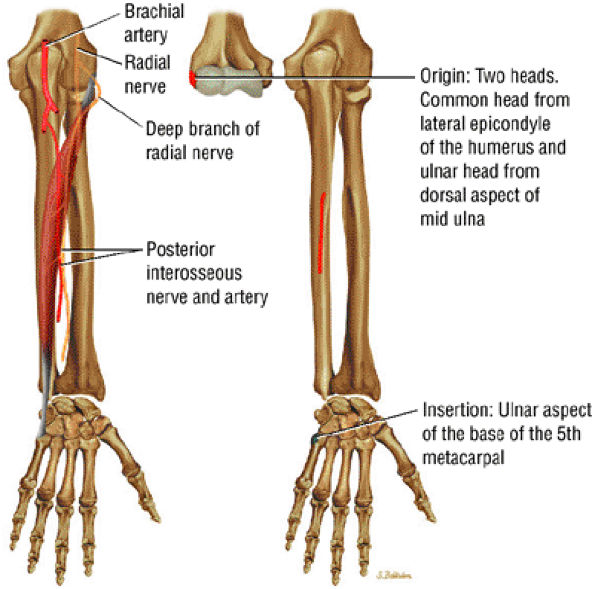

FIGURE 10.15 ● EXTENSOR CARPI ULNARIS The extensor carpi ulnaris tendon extends and adducts the wrist. It is commonly affected in tendinosis and tenosynovitis as it passes through the groove on the distal ulna. Subluxation of the extensor carpi ulnaris can also occur at this location related to disruption or insufficiency of the ligament that covers the tendon in this groove. The extensor carpi ulnaris tendon subsheath is a component of the triangular fibrocartilage complex.

|